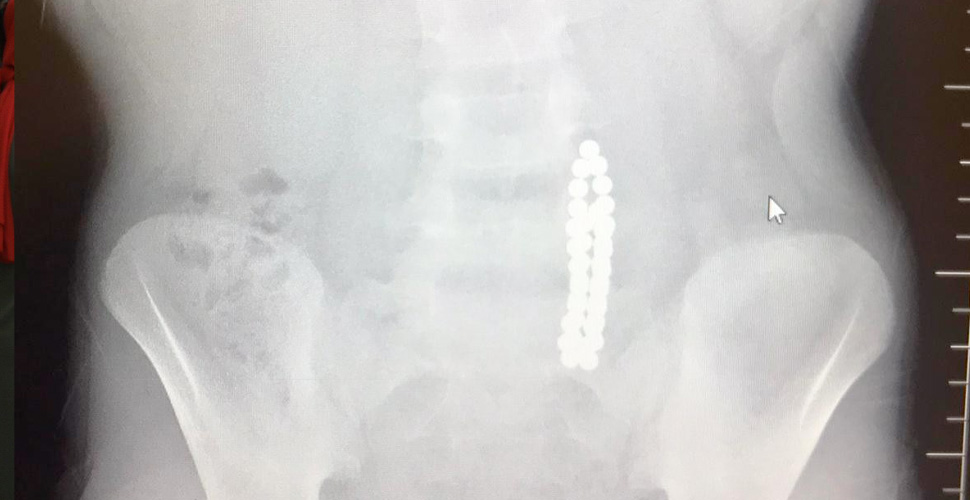

Beylikdüzü’nde 9 yaşındaki bir çocuk ailesinin haberi olmadan neodyum adı verilen stres bilyeleri olarak da bilinen 42 adet mıknatısı yuttu. Birkaç gün sonra şiddetli karın ağrısı ve kusma şikayeti ile hastaneye gelen çocuğun röntgeni çekildi. Röntgen filminde çocuğun midesinde boncuklar halinde yabancı bir cisim tespit edildi. Bağırsağını delen cismi fark eden Beykent Üniversitesi Çocuk Cerrahisi Uzmanı Prof. Dr. Ali Çay çocuğu ameliyata aldı. Yapılan ameliyatta çocuğun bağırsaklarından rengarenk şekilde 42 adet neodyum çıkarıldı.

“MIKNATISLARI YUTTUĞUNU RADYOGRAFİDE GÖRDÜK”

Konuyla ilgili konuşan Prof. Dr. Çay, yutulan cisimlerin normalde sindirim sistemi ile çıkabileceğini ancak çoklu mıknatısların bağırsaklarda delinmeye neden olabileceğini ifade ederek, “Bizim hastamız yaklaşık 42 tane bu mıknatıstan yutmuş çeşitli hastanelere müracaat etmiş. Burada yapılan incelemelerde çekilen filmlerde tesadüfen bu mıknatısları yuttuğunu biz radyografide gördük hastamızı ameliyata aldık. İnce bağırsak uç kısmında delinme oluşturmuştu. Biz bu mıknatısları çıkardık” dedi.